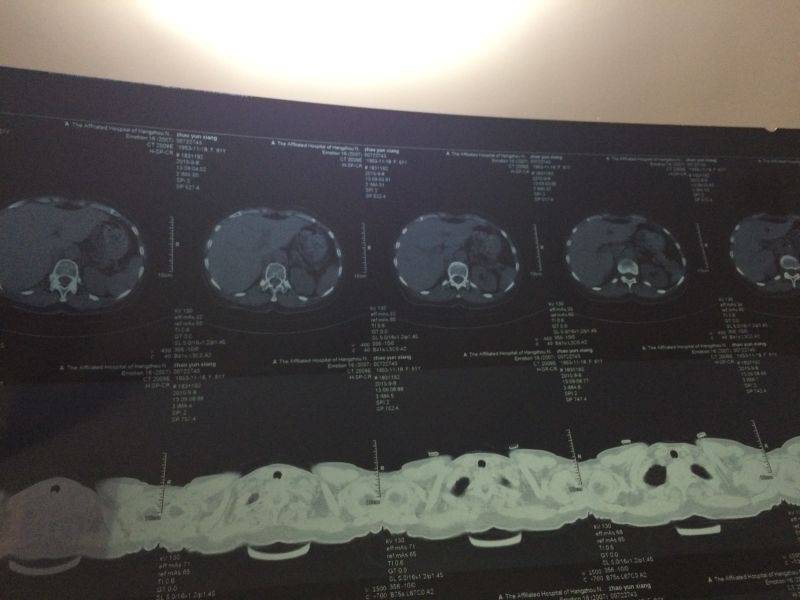

这个具体的情况是如何的人,谁帮忙看看?

为什么不去取活检,确诊病情,就这么出院了?从病历上看,还是比较乐观的,建议到医院进一步确诊。个人建议

病情的确诊最好是取活检确诊,进一步做检查吧

到医院做一个确诊,尽早的接受治疗